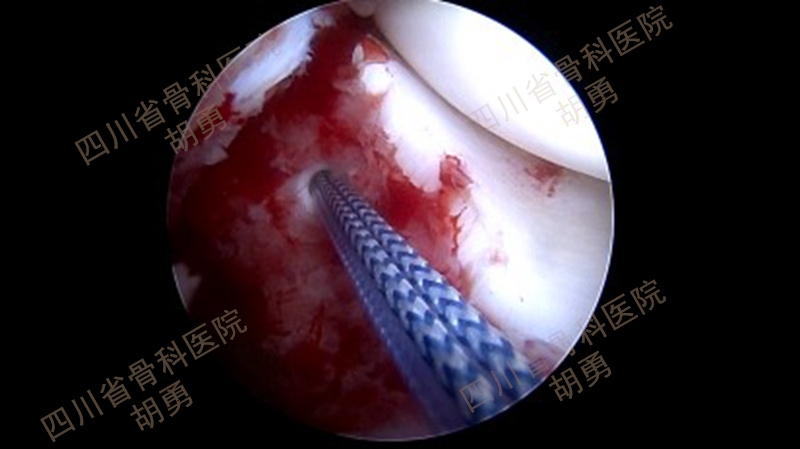

从2016年4月~2020年12月,共计25名4~11岁患儿接受了镜下手术,平均年龄9.2岁。在全部患儿中,有10名病程超过两周,属陈旧性骨折。作者采用了肩袖的镜下缝合桥技术,通过术中透视,所有的操作均在生长板上完成:在骨床后壁胫骨内、外侧髁间嵴连线中点植入一枚内排锚钉,用成角90°半月板全内缝合器将0号PDS线环在前叉韧带后内、后外两侧穿过撕脱骨块,将锚钉自带两种颜色的双骨科高强缝线分别从前叉韧带两侧过线穿过线环,并牵拉穿过撕脱骨块到达骨折表面。再将双色缝线混合引入胫骨骨床提前钻好的两个骨隧道中,双向交叉压迫于撕脱骨块上,调整骨位及缝线位置并拉紧缝线后,完成镜下复位。拉出胫骨隧道后的缝线使用一枚外排钉固定于生长板上。术毕,镜下缝线桥复位及内固定如图1所示,术前及术后MRI如图2和图3所示。术后2~3天,在疼痛缓解的前提下,开始主动康复训练。

图1 缝线桥复位及内固定术后镜下所见

将拉出入口备用的前内及前外骨隧道PDS线环分别引入关节内,使用环钳穿过线环,引入两色骨科高强线各一根,从胫骨隧道拉出线环,将两色缝线各一根混合引入前内及前外骨隧道,如图19所示。调整撕脱骨块骨位及交叉压迫于骨面的缝线位置和牵拉张力后,镜下所见如图1所示。